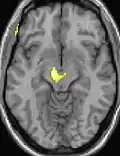

![]() |

| Tomografia PET mostrando áreas ativadas na dor. | ||

| VBM mostrando diferenças estruturais entre cérebros | ||